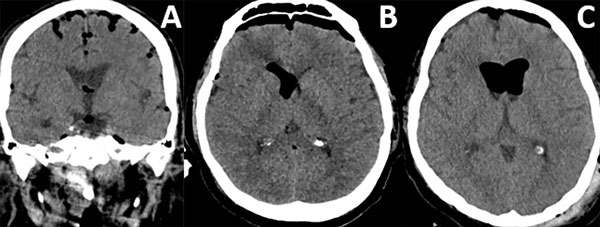

Patrones y grados de NE: NE subdural (Figura 1), se clasificó en 3 grados: leve (menor al espesor óseo), moderado (entre una vez y dos veces el espesor óseo) y severo (dos o más veces el espesor óseo). NE subaracnoideo (Figura 2), se clasificó en 3 grados: leve (confinado a cisternas basales), moderado (cisternas supratentoriales predominio unilateral), severo (generalizado). NE ventricular (Figura 3), se clasificó en: leve (en IV y/o III ventrículo), moderado (alcanzó VL), severo (alcanzó y dilató los VL).

Figura 3. Neumoencéfalo ventricular. A) Leve. B) Moderado. C) Severo.